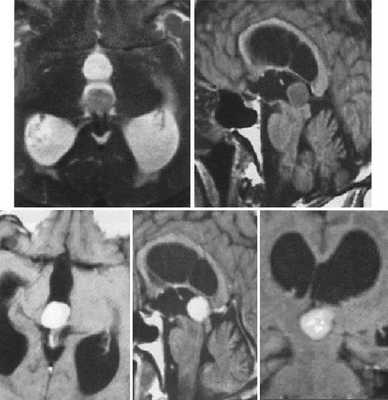

Пинеоцитома. На Т2 ВИ опухоль состоит из двух участков разной интенсивности МР-сигнала: высокой в передних отделах и низкой в задних. Четкость и линейность перехода свидетельствует о кистозном характере строения опухоли. Различия интенсивности МР-сигнала от жидкости в передних и задних отделах опухоли обусловлены эффектом «седиментации» белковых компонентов (вероятнее компонентов крови), опускающихся вниз при положении головы пациента на затылке.

Пинеоцитома. МРТ в режиме Т2 и Т1 выявляется солидного строения опухоль задних отделов III желудочка мозга. На фоне в/в контрастирования определяется выраженный и достаточно гомогенный характер контрастирования опухоли.